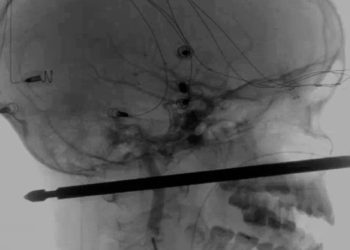

Xavier Cunningham, un niño de 10 años residente en Harrisonville (Misuri, EE.UU.) sufrió el pasado sábado un aparatoso accidente en el jardín ...